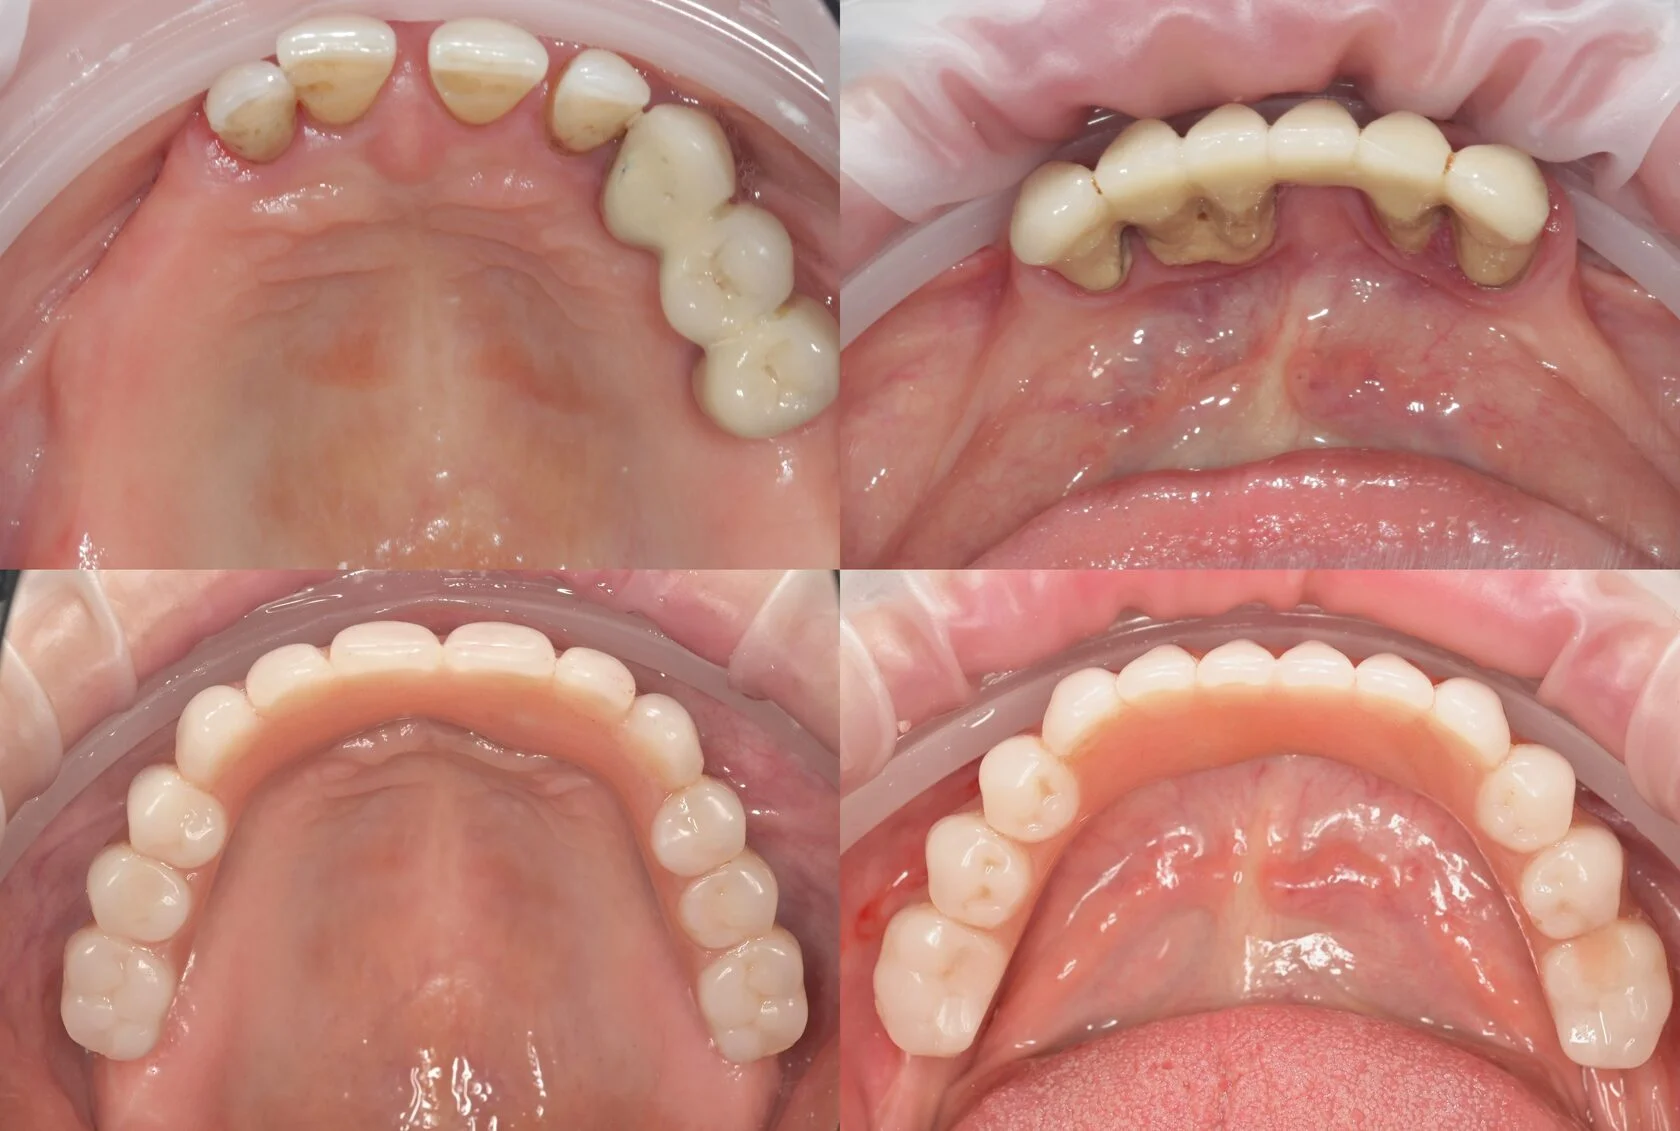

«Говорили, что это невозможно». Пациентка долго слышала, что в её ситуации полноценное восстановление зубов невозможно или потребует множества этапов и длительного лечения. Это останавливало её от решения проблемы на протяжении многих лет. Частичное отсутствие зубов на верхней и нижней челюсти требовало функционального и предсказуемого решения.

На консультации мы провели подробную диагностику и нашли варианты лечения. В итоге была выполнена тотальная реабилитация. В день операции установлены имплантаты и несъёмные конструкции.

Уже через 4 часа была восстановлена жевательная функция и anti-age-эффект за счёт правильной опоры мягких тканей.

Пациент долго откладывал лечение, сомневаясь в необходимости серьёзного вмешательства и опасаясь сложной операции. Но со временем неудобства и ограничения в повседневной жизни, особенно во время приёма пищи, стали перевешивать сомнения.

На консультации мы подробно разобрали все этапы лечения, обсудили возможные риски и подобрали понятный и комфортный план. В итоге была проведена реабилитация верхней и нижней челюсти по концепции All-on-6 с немедленной нагрузкой. В день операции установлены имплантаты и несъёмные конструкции.

Сегодня пациент признаётся, что зря так долго сомневался — результат превзошёл его ожидания.

Долгое время откладывал лечение, потому что боялся сложной операции и долгого восстановления. Жил с постоянным дискомфортом и ограничениями в питании, но не решался сделать первый шаг. Длительное отсутствие зубов на верхней и нижней челюсти привело к потере жевательной эффективности и опоры мягких тканей.

На консультации мы подробно разобрали все этапы лечения, ответили на все вопросы и подобрали комфортный и безопасный план. По протоколу All-on-4 на обеих челюстях установлены несъёмные конструкции.

Уже в день операции пациент получил новую улыбку. Обеспечена стабильность прикуса, полноценная функция и выраженное улучшение лицевых пропорций за счёт восстановления опоры тканей.